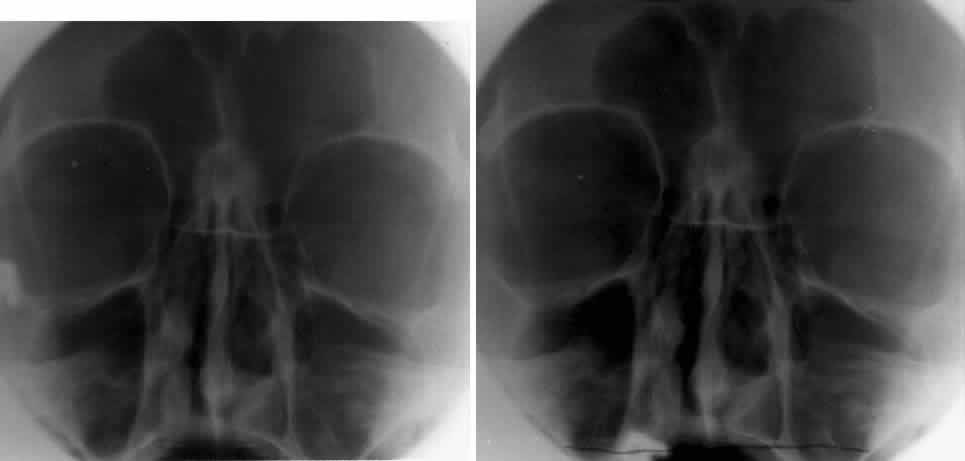

CALDWELL PROJECTION

In 1918 the evaluation of the frontal and ethmoid sinuses prompted Caldwell9 to describe a projection (Fig. 3) that eliminates the superimposition of the sphenoid bone on these paranasal sinuses. The patient is positioned with both the nose and forehead against the x-ray cassette while the x-ray beam is directed downward 15 degrees to 23 degrees to the canthomeatal line.5,6,9 This orientation also projects the petrous bones inferior to the orbit, thus avoiding obscuration of the orbital structures. As in the Waters view, the Caldwell view is a posterior-anterior projection. This excellent view of the frontal and ethmoid sinuses also allows good visualization of the orbital rims, greater and lesser sphenoid wings, lacrimal gland fossa, medial orbital wall, and both the superior and inferior orbital fissures.10 The innominate line is prominent in this view and represents the depression on the temporal surface of the greater wing of the sphenoid bone where it forms the medial wall of the temporal fossa or lateral wall of the orbit. This innominate line can be straight, end with a medial right angle turn, or continue inferiorly to form the outline of the pterygoid plate.8 A lack of continuity of the innominate line suggests a fracture of the lateral orbital wall.

Fig. 3. A. Schematic showing positioning for a Caldwell projection. (CM, canthomeatal line; CR, central ray) B. Radiograph of a Caldwell projection. The petrous ridge is positioned at the orbital floor. Detail of the orbital floor and maxillary sinus is blocked. C. The radiograph is taken at a steeper angle so the petrous ridge is now positioned lower within the maxillary antrum. (a, frontal sinus; b, innominate line; c, inferior orbital rim; d, posterior orbital floor; e, superior orbital fissure; f, greater wing of sphenoid;g, ethmoid sinus; h, medial orbital wall; i, petrous ridge; j, zygomatic-frontal suture; k, foramen rotundum) (A; Rao VM, Gonzalez CF: Plain film radiography and polytomography of the orbit. In Gonzalez CF, Becker MH, Flanagan JC [eds]: Diagnostic Imaging in Ophthalmology, pp 1–7. New York, Springer Verlag, 1986)

The Caldwell view of the floor gives the best information concerning the posterior orbital floor. Again, this is because the posterior floor is more tangential to the x-ray beam than the more anterior orbital floor. Evaluation of the orbital rim may be limited by superimposition of the rim on the orbital floor or petrous bones. This projection can cause confusion because the floor is evaluated from anterior to posterior. The floor projects below the rim anteriorly, about equal with the rim at the midorbit, and superior to the rim in the posterior orbit.10 The orbital floor and underlying maxillary sinus can be adequately evaluated by using both the Waters and Caldwell views.